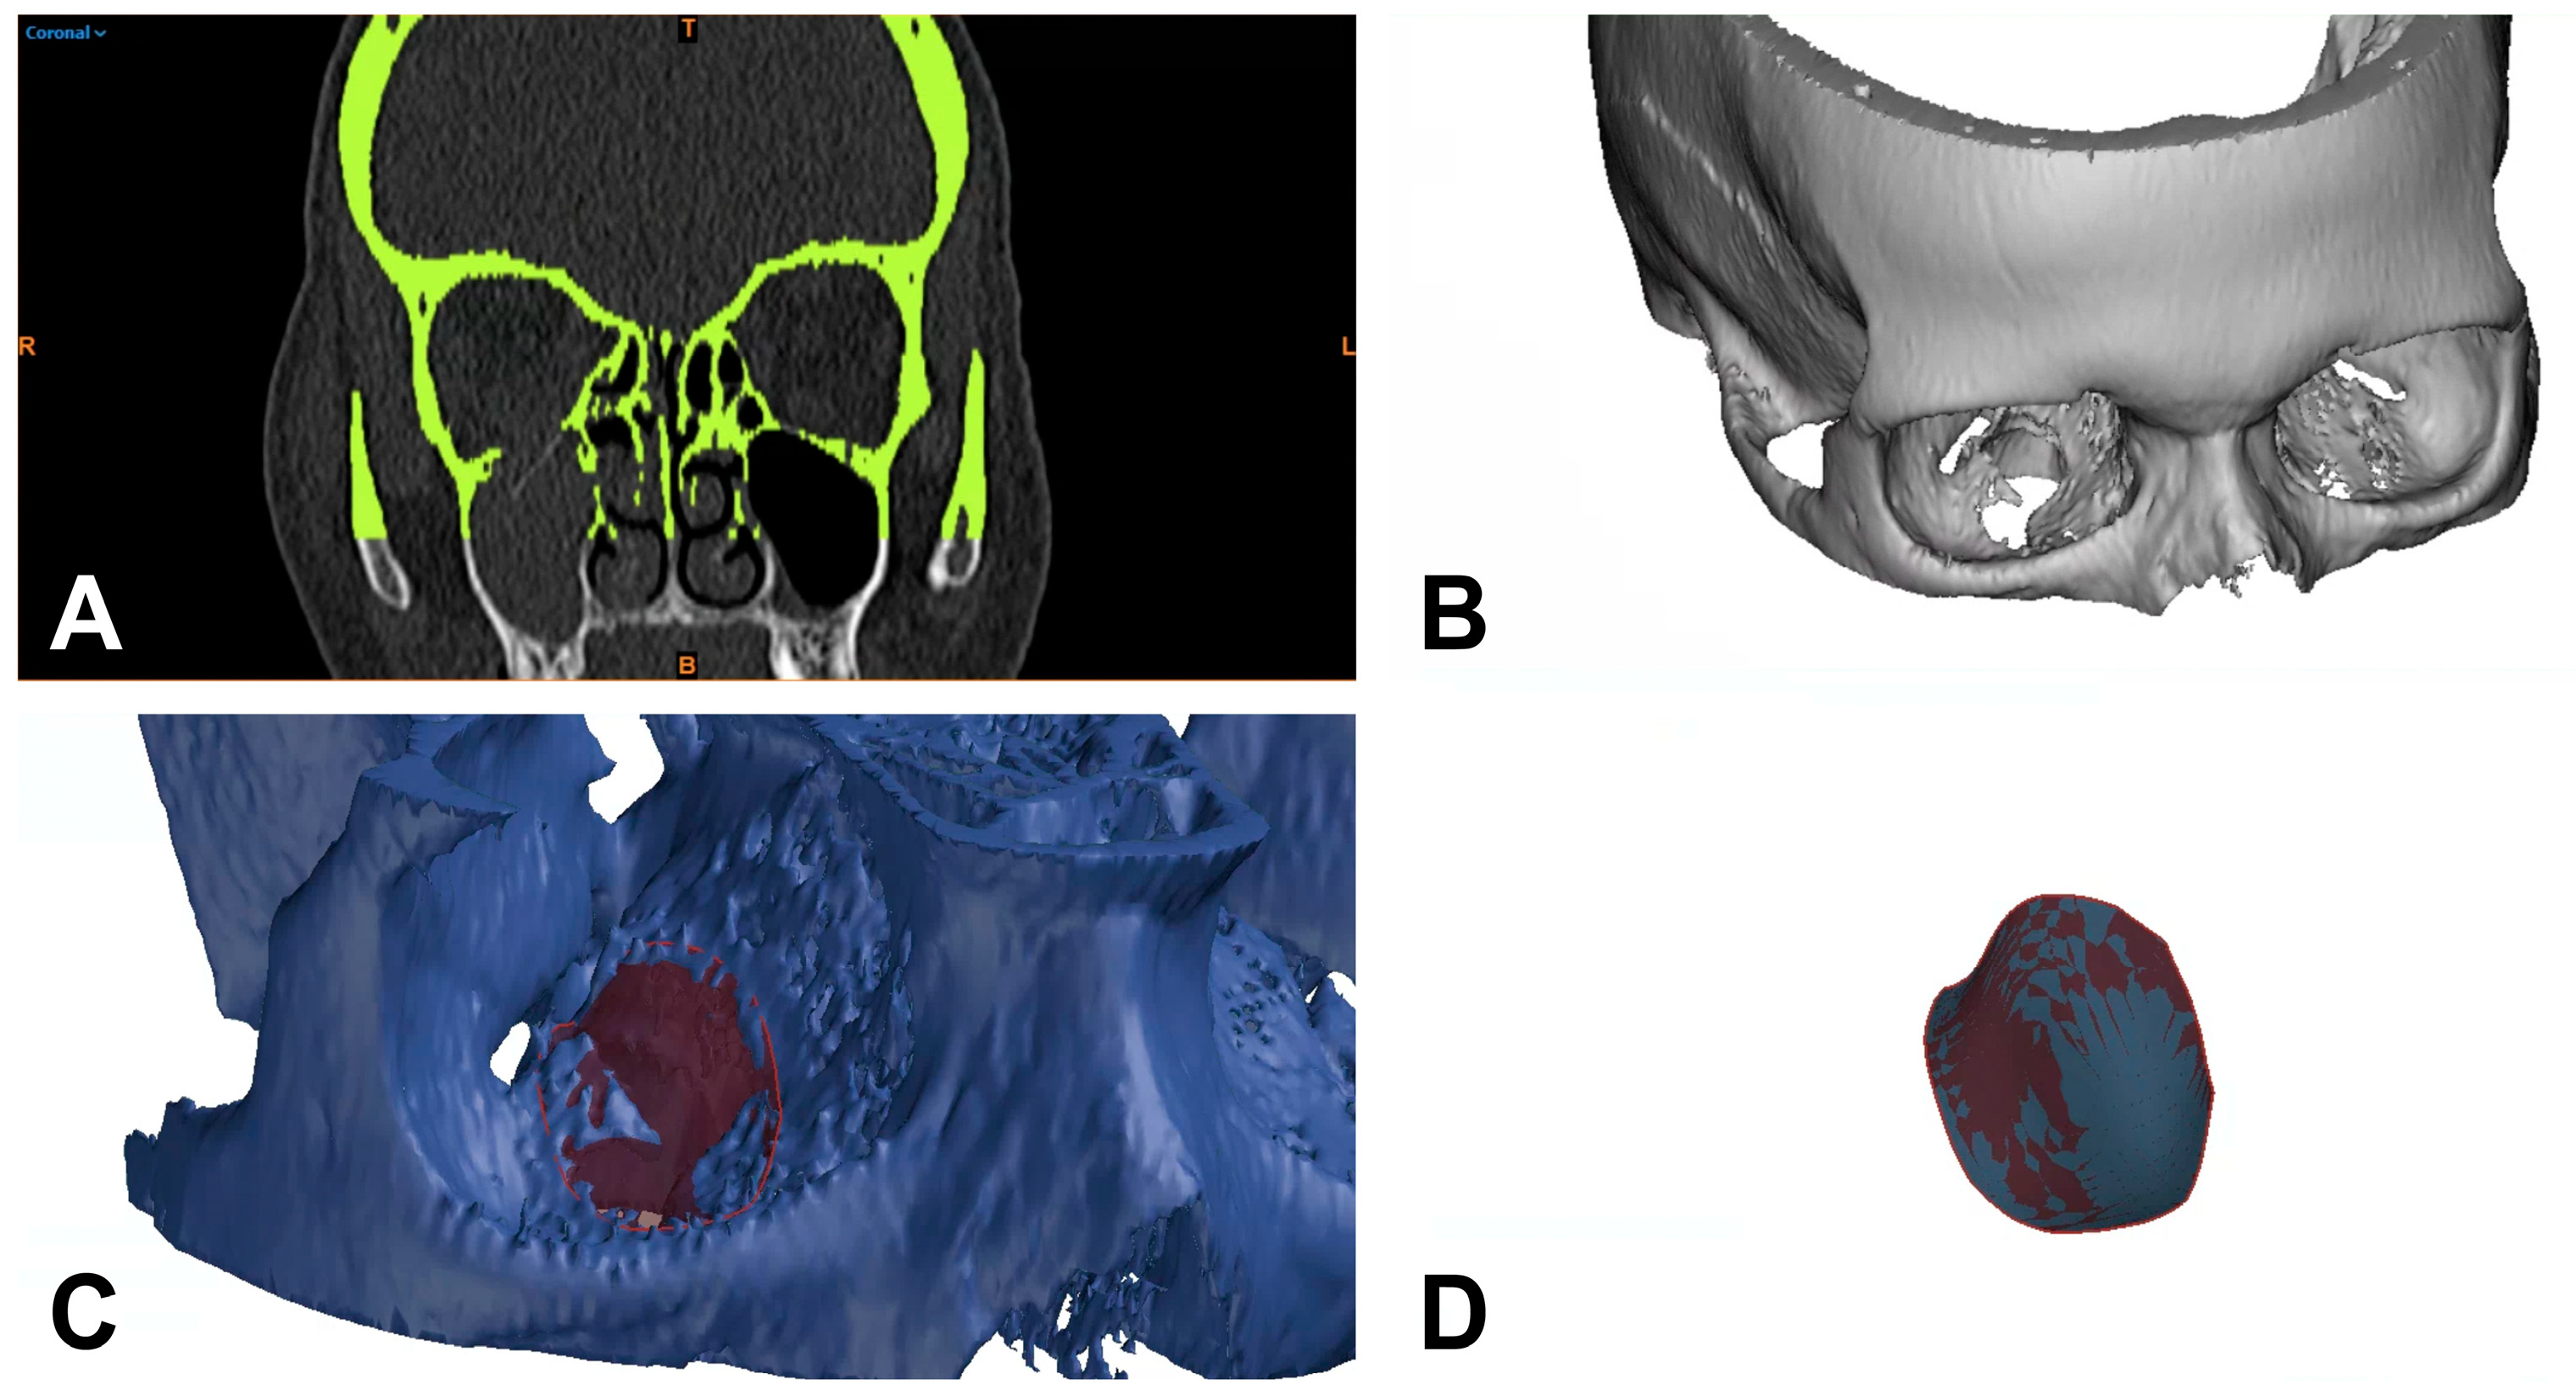

2.3. 3D-Based Measurements of Orbital Floor Fractures